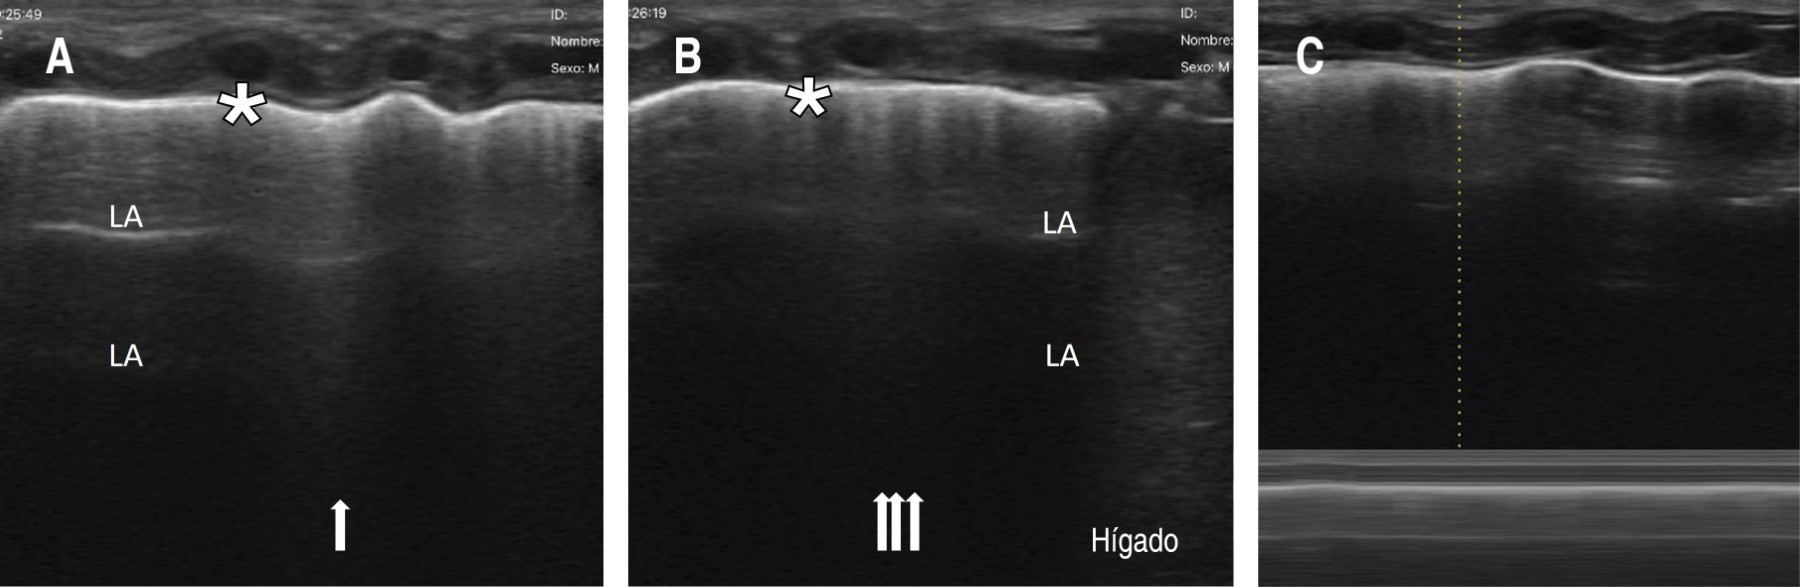

Se procede a realizar UP, como parte del protocolo SAFE,1 observando en la región medial y basal derecha la presencia de neumotórax (Figura 1); mientras que en la región lateral derecha y en el hemitórax izquierdo no se identificaron anormalidades. Cabe señalar que el neumotórax no era visible en la radiografía anteroposterior de tórax, por lo que se solicita radiografía lateral en la cual sí se evidencia el neumotórax anterior (Figura 2).

Figura 2